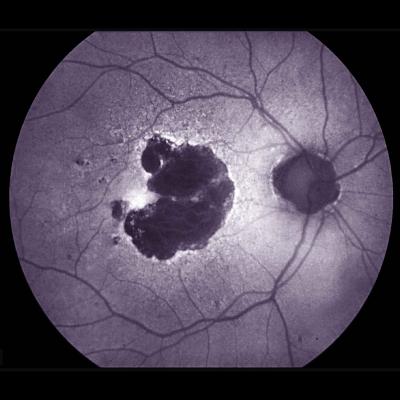

Retinal photo showing large area of geographic atrophy. Image credit: NEI.

Dry AMD affects the macula, the part of the eye’s retina that allows for clear central vision. In people with dry AMD, patches of light-sensing photoreceptors and their nearby support cells begin to die off, leaving regions known as geographic atrophy. Over time, these regions expand, causing people to lose more and more of their central vision. Microglia, immune cells that help maintain tissue and clear up debris, are present at higher levels around damaged retinal regions in people with dry AMD than in people without AMD. Scientists have suggested that inflammation – and particularly microglia – may be driving the expansion of geographic atrophy regions.